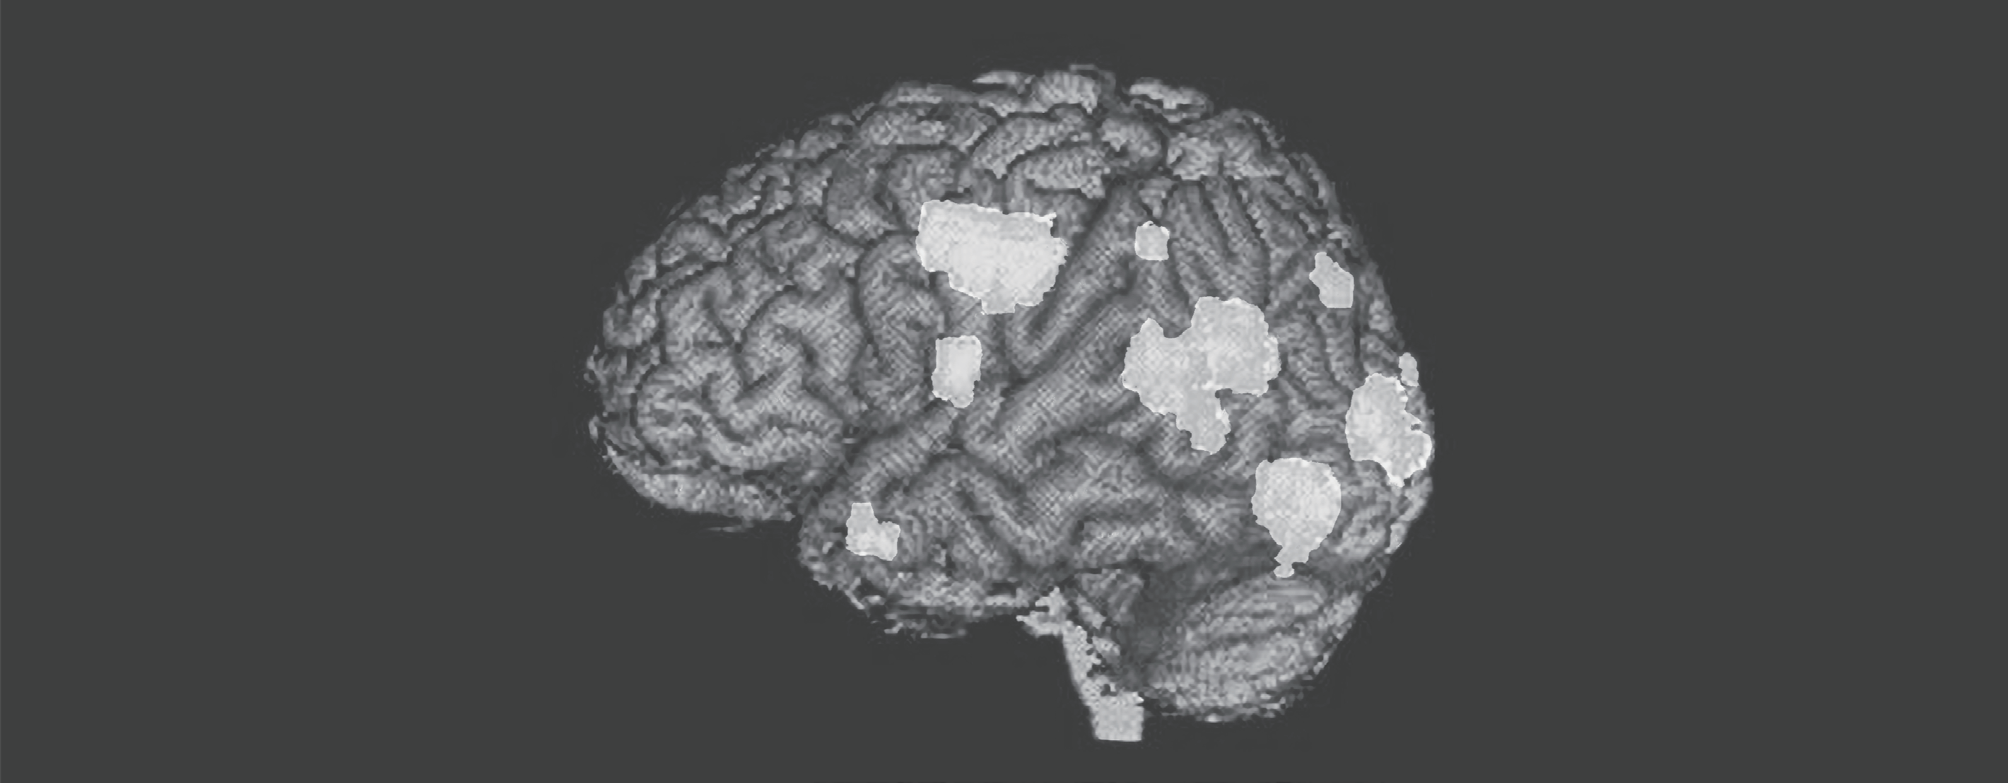

一位23岁的精神分裂症患者出现幻觉时的脑部扫描图像。截至目前,抗精神病药物都是通过阻断多巴胺受体发挥作用的,这可以减轻症状,但也存在严重缺陷